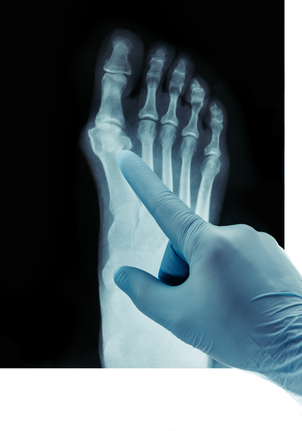

Před zákrokem je potřeba rentgenový snímek nohy pod zatížením. Pouze za podmínek zatížení lze přesně určit úhel mezi prvním a druhým metatarzem a pomáhá znázornit deformity prstů a nestabilitu sousedních kloubů.

Měly by být také zkontrolovány jakékoli příznaky osteoartrózy.